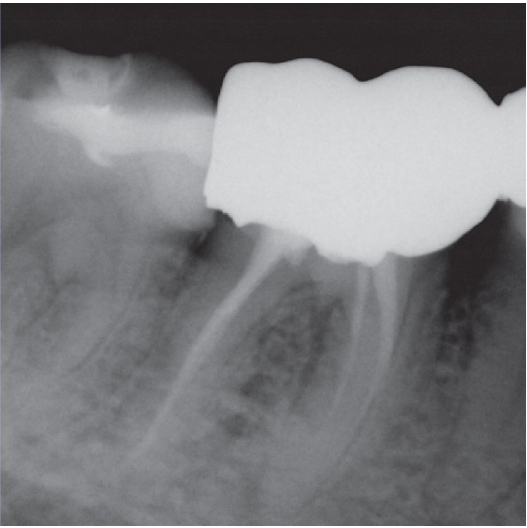

Before

Before Root Canal treatment